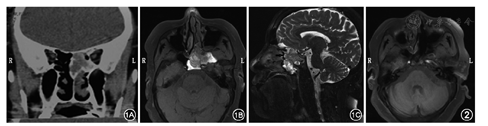

患者女,66岁,因左侧头痛2年,加重3 d于2014年11月3日入院。患者2年前出现双侧交替鼻塞、流黄涕,左侧较重,伴有头晕、头痛,未治疗。入院前3 d自觉头痛加重,就诊于当地医院,行鼻窦CT检查(图1A),考虑左侧后组筛窦及蝶窦占位性病变。既往无高血压、糖尿病等。入院后行鼻窦MRI平扫(图1B、图1C),提示左侧鼻腔、筛窦、蝶窦内、左侧中颅窝底异常信号影,侵及左侧蝶窦、筛窦、左侧颅底骨质,考虑占位性病变。行电子鼻内镜检查,见左侧鼻腔总鼻道内光滑新生物。入院后第3天在全麻下行鼻内镜下左侧鼻腔肿物切除术,左侧筛窦、蝶窦开放术,左侧蝶窦内肿物切除术。术中见左侧鼻腔总鼻道内光滑肿物生长,切除鼻腔内肿物送冰冻,回报为息肉。切除部分中鼻甲及上鼻甲后,暴露蝶筛隐窝,见蝶窦自然口已扩大,窦口周围及蝶窦内大量分叶状肿物,质韧,切除部分肿物组织再次送快速病理,回报为IP。电钻适当扩大蝶窦前壁,尽量暴露蝶窦,向内达蝶窦中隔,向下达蝶窦底壁,向外达中鼻甲平面,术中见肿物根部位于蝶窦底壁,将肿物完整切除后,磨除部分底壁表面骨质。开放后组筛窦,见后筛内黏膜水肿,部分黏膜呈息肉样变,未见肿物生长。术后病理回报:鼻腔息肉,蝶窦IP,无恶性变。患者术后2 d抽出鼻腔填塞物,无并发症,术后7 d出院。鼻内镜下定期复查,术后6个月复查电子鼻内镜,可见蝶窦窦腔内少量脓性分泌物,未见肿物复发。术后16个月复查鼻窦MRI(图2),未见肿物复发。现继续随访中。

鼻腔鼻窦病变最常用的影像学检查方法为鼻窦CT扫描,而CT检查不易区分IP与鼻窦炎,不能清楚地显示肿瘤的完整轮廓,与其他肿瘤鉴别困难[7],而MRI检查具有无辐射损伤、软组织分辨率高及多平面成像等优势,能将IP与鼻窦炎性疾病鉴别开来,并更好地确定病变范围,清晰地显示肿瘤内部构架的信号改变[8]。1985年,Barnes等[9]最先描述了IP在MRI上具有明显特征性高低信号相间条纹影,并称为脑回状条纹影(convoluted cerebriform pattern),2004年,Maroldi等[10]也研究了此条纹影,认为在T2WI及增强T1WI序列能观察到此影像。另外,在部分IP患者的矢状面MRI,可见肿瘤边缘呈波浪状,即"贝壳征(shell sign)",可能是由于鼻腔前后径较大,肿瘤可无障碍生长,形成了虽为良性肿瘤但无包膜的桑葚样外观,此征象在T1WI平扫及增强扫描均可清晰显示。本例患者术前鼻窦MRI平扫中,T2WI(图2B)呈短T1短T2异常信号,即显示出特征性的高低信号相间的脑回状条纹影;而矢状位亦可见贝壳征(图2C)。